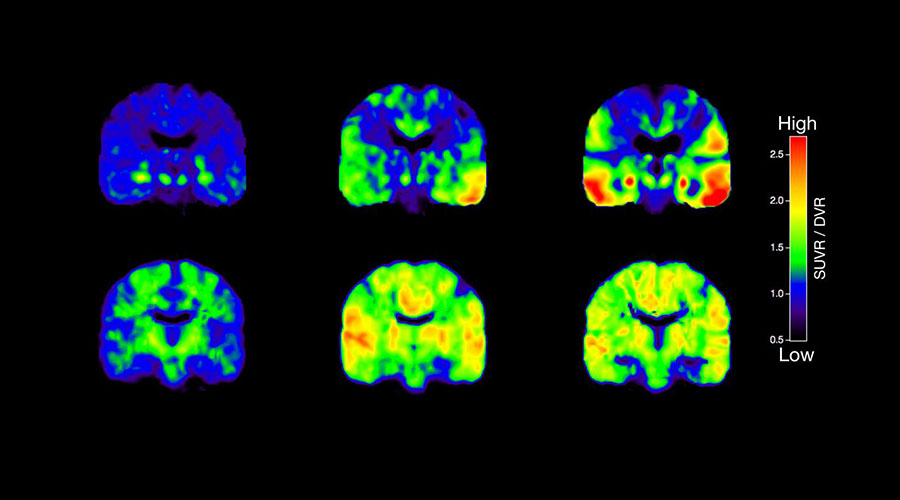

Böyle olunca hastanın nefes alma derinliğine bağlı olarak alınan kesitlerde; ( Yukarıdaki resimde görüldüğü gibi ) resmin sağında olan kesit soldakinin devamı olmayıp yuvarlak beyaz renkte olan akciğer lezyonu hastanın düzenli nefes almaması nedeniyle atlanmıştır. Dolayısıyla alınan bir sonraki kesit gerçekte bir önceki akciğer alanının devamı olmayabilir ve orada bir lezyon varsa klasik tomografi yöntemi ile bu atlanmış olur.